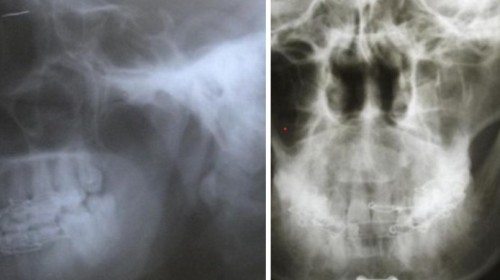

During road traffic accidents there are many dental injuries and Facial bone injuries. Because of these injuries patients will have bleeding and deformity of the face and pain. Many people cannot speak and cannot eat properly. So to correct all these things we need surgical procedures.